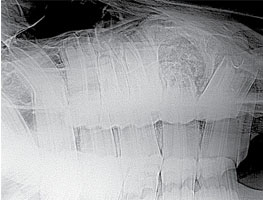

A 3-year-old Quarter horse gelding in good condition had a swelling on his right maxilla that had been increasing in size (Fig. 49). There was nasal discharge with a foul odor coming from the right nostril. The maxilla was swollen in the area of the 107, however the clinical crown looked normal when examined, and there was no mobility of any teeth in the arcade (Fig. 52). There was a small amount of feed packing on the buccal side of the 107. An open mouth lateral oblique radiograph was taken to isolate the enlarged area over the 107 (Fig. 51). Also taken was a dorsal/ventral offset radiograph showing a clear image of the abscess involving the 107 (Fig. 50). It was large and spherical in shape surrounded with dense sclerotic bone. Most root abscesses involving the upper 7’s rupture and drain to the outside of the maxilla. In this case the drain tract was formed into the nasal cavity, which is unusual. This accounts for the purulent nasal discharge coming from the right nostril. The area was surgically prepped, and local anesthesia was infused in the area to desensitize the skin and subcutaneous tissue (Fig. 53). A maxillary nerve block was performed earlier for the oral extraction which lasts approximately 90 to 120 minutes. A skin flap was created first; then the subcutaneous tissue and periosteum were elevated off the bone and transfixed proximally. A 2cm Fortner drill bit was used to make the hole through the maxilla at the proximal end of the abscess. The bone was sclerotic and thick in this area due to the chronic abscess. The hole needs to be big enough to allow a curette to be manipulated in the abscessed area. After debridement of all necrotic tissue and fragments, the periosteum, subcutaneous tissue, and skin were replaced and sutured (Fig. 54). This area should granulate in quickly if all necrotic tissue and fragments have been removed. The communication with the nasal cavity was a small drain tract that was debrided and sutured. The nasal discharge should cease if the drain tract has been resolved. The 107 was extracted orally with the horse standing using sedation and local anesthesia (Fig. 53). This tooth was not difficult to extract because of lack of reserve crown and damaged periodontal attachment. After the tooth was removed, the alveolus was examined for debris and fragments. There were numerous tooth particles about the size of small buckshot laced throughout the necrotic tissue in the abscess.